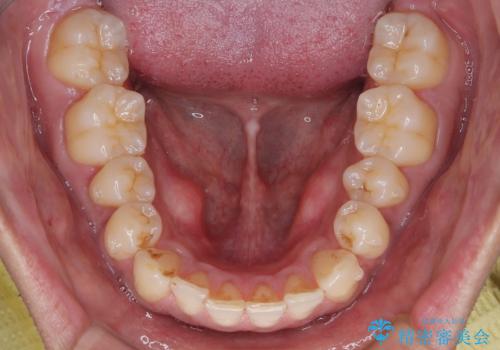

診察したところ、上下顎前歯部に軽度の叢生(ガタつき)が認められます。

目立たない装置を希望されたのでインビザライン ライトパッケージで治療を行うことになりました。

矯正治療後は、後戻りを防ぐために リテーナー(保定装置) を使用していただきます。

以前の矯正で後戻りを経験されているため、患者様にも重要性をご理解いただき、

しっかりと保定していただくことで美しい歯並びを長く維持できます。